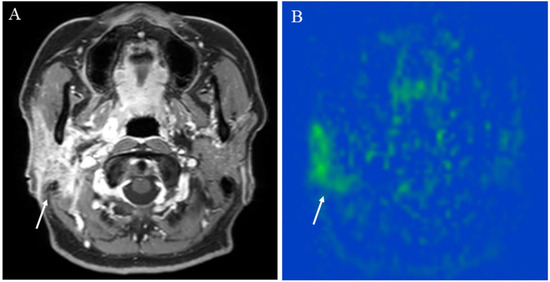

5.1.1. Inflammatory Lesions: Sialadenitis and Dacryoadenitis

5.1.2. Hypervascular Lesions

5.1.3. Salivary Gland Tumor Differentiation: Malignant Salivary Tumors, Pleomorphic Adenomas, and Warthin’s Tumors